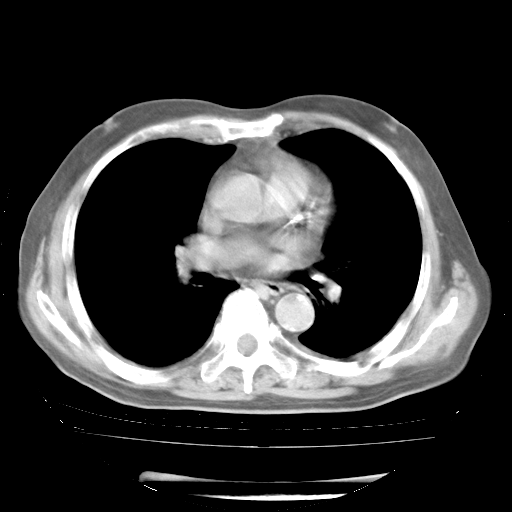

4月28日肺部CT——再次出现类似去年5月9日——透光度降低,“间质性”改变。

个人阅读4.14日肺部CT平扫:纵隔窗无异常,但肺窗示:双下肺内、后基底段有片絮状侵润影,部位以后基底段为著,以间质改变为主,呈急性肺泡炎征像,和首次住院影像学有相似之处。仅是个人读片,明日请相关专家再读片哈。其它建议同上。

1、108#的是4月14日的胸部CT(发此贴时还没看着28日的CT)。14日的胸部CT其实已经出现改变(如108#所述),个人认为28日的胸部CT除纵膈窗疑似有双侧胸膜增厚或少量胸积液(可行胸部B超明确)外,与4月14日对照病变有所加重;2、已经给予“异烟肼、利福平、乙胺丁醇”抗痨治疗?如果是,甲强龙80mg可缓慢减量;如果环磷酰胺已停用,暂不使用;3、中性粒细胞92%,明显升高,目前体温情况?注意合并细菌感染可能,使用左氧氟沙星情况下,是否联用B-内酰胺类抗菌药物?另外是查免疫全套非风湿全套。

今请临免主任会诊后认为:4月14日胸部CT已有双下肺间质性改变。患者病情复发多系激素减量过快不正规所致。目前甲强龙80mg/日,一周后酌情开始减量,不易过快。环磷酰胺若已停用,暂不使用。他同意目前抗菌药物使用,但应考虑是否加用B-内酰胺类抗菌药物(中性细胞明显增高);2、结核复发目前依据不足;3、若免疫全套各项指标正常,考虑多系特发性肺间质炎可能大。4、加强支持,并注意保护胃黏膜。